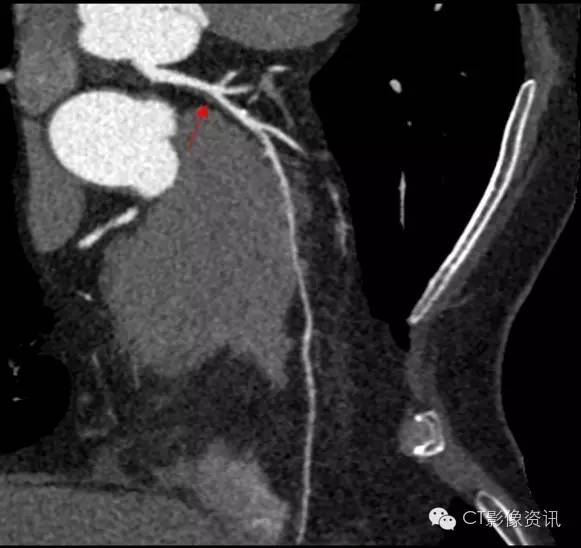

冠脉血管问题典型表现就是左心前区的不适、憋闷,疼痛感,甚至会放射至左后背,这不,老陈就出现了明显症状,咱们来看看:

首先我们发现了一个问题,前降支血管走进了心肌中,这代表着即使没有斑块问题,在活动时也有可能出现不适的情况。但是到了Revolution CT这里,怎么会放过它哪!但是,它是不是真正引起老陈临床症状的原因?

发现了另一处病变:VR图清晰显示第二个问题:LMA与LAD交界处的狭窄

找到病因:CPR及轴位图像清晰显示狭窄原因:斑块形成

认清成分:分别测量斑块的不同密度区:发现了斑块内的平均CT值为7.5Hu,最低CT值为-19Hu,我们确定这是一个软斑块,为“易损斑块”,即是会干坏事的斑块。

小科普一下,这里说的易损斑块可是非常危险的因子,它是心血管急性事件的重要原因。相对普通CT来说,确认是它可不是一件容易的事情,但是在Revolution CT的火眼金睛下,一切干坏事的都会清楚的暴露出来的!赶紧找心内科医生吧!